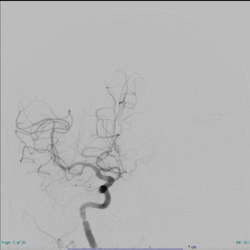

図. 管撮影:治療前(左)は血管が途絶しているが、治療後(右)では途絶していたところから血管が描出されるようになった

一方で、時間がたって場合には再開通させても末梢の血流が改善しないNo-reflow現象が知られています。

当研究室では、再灌流障害の病態を研究し、治療薬の開発に携わっています。